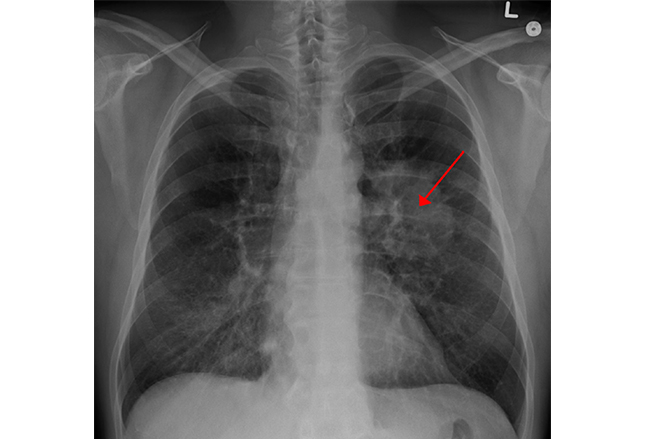

胸腔X光显示左肺上叶大肿瘤(红色箭头)